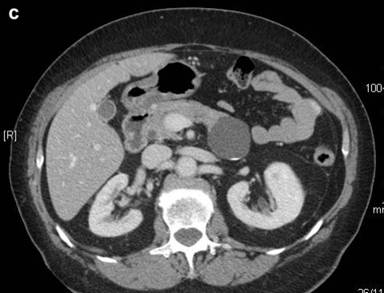

Then, abdominal computed tomography (CT) performed six months later showed that the cystic lesion did not increase in size, but had a 12.0 mm lamellar calcification on the posterior wall and impressed the left renal vein, without any signs of invasion of the surrounding tissues (Figure 1bc). The cystic lesion had no increased tracer uptake at 18F-FDG-positron emission tomography (PET). The patient had no symptoms related to the pancreatic lesion and blood tests were all normal. Serum carbohydrate antigen 19-9 (CA 19-9) and carcinoembryonic antigen (CEA) levels were normal.

Figure 1. a. The pancreatic tail cyst at MRI scan. b. c. CT scan showing a 4 cm cystic fluid mass arising from the tail of the pancreas, with well defined margins and a lamellar calcification on the posterior wall. |